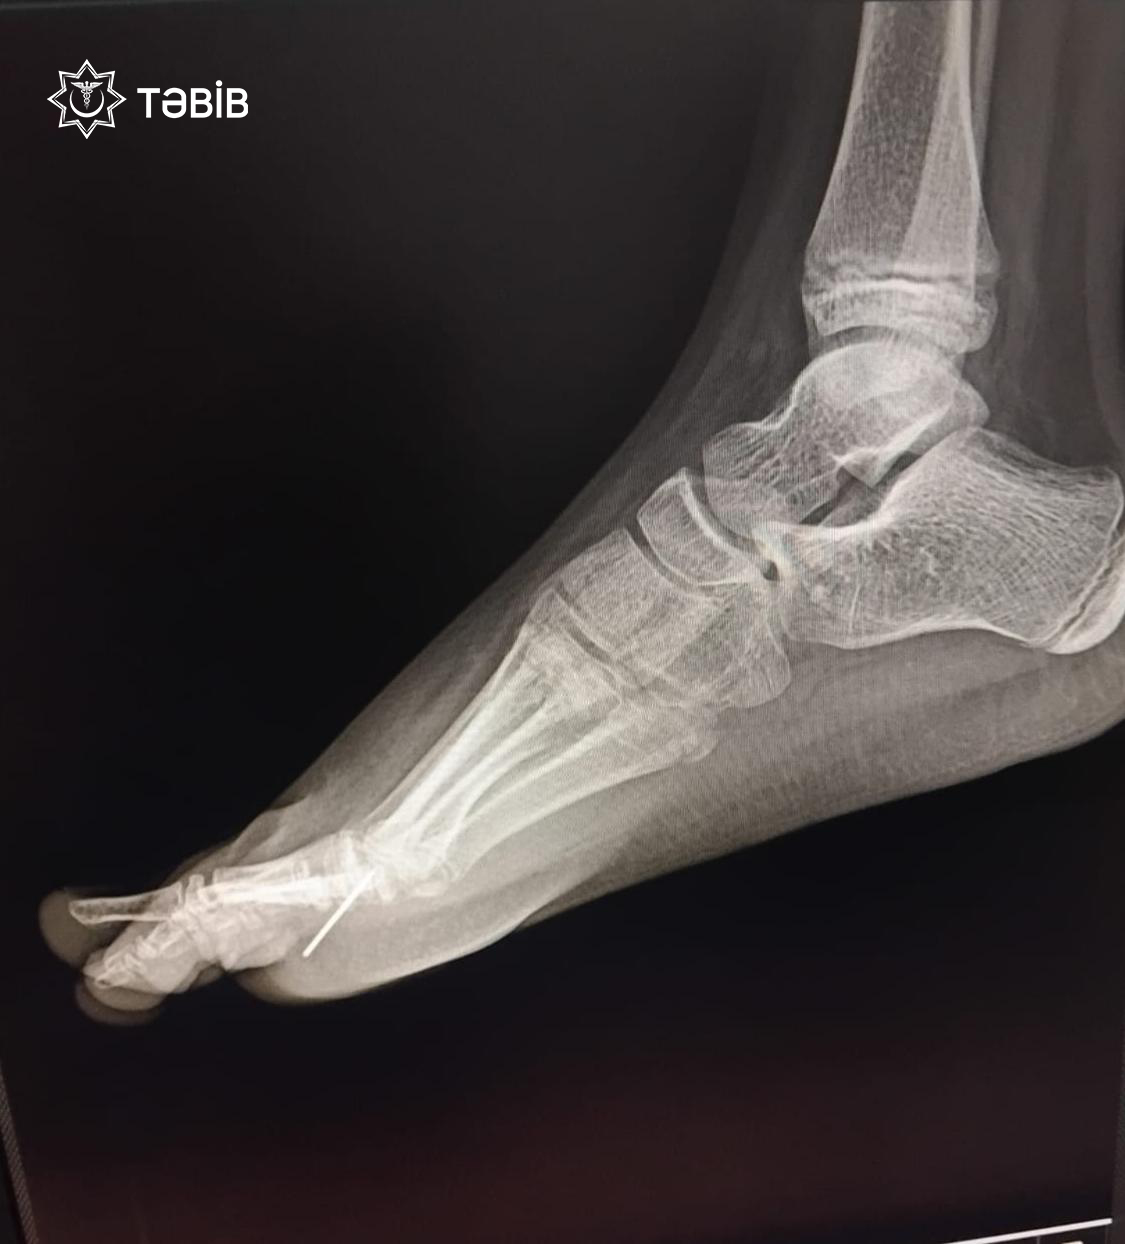

“Ayağında davamlı ağrı və şişkinlik şikayətləri ilə xəstəxanaya gətirilən 11 yaşlı uşağın rentgen müayinəsi zamanı sağ ayağının pəncə nahiyəsində yad cisim aşkarlanıb”.

“TƏBİB-in tabeliyində fəaliyyət göstərən Binəqədi Tibb Mərkəzində müayinədən keçən 2014-cü il təvəllüdlü uşaq (qadın cinsli) cərrahi əməliyyat olunub və pəncə nahiyəsindəki yad cisim – iynə parçası təhlükəsiz şəkildə xaric edilib.